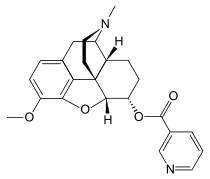

- Esters of morphine opiates: slightly chemically altered but more natural than the semi-synthetics, as most are morphine prodrugs, diacetylmorphine (morphine diacetate; heroin), nicomorphine (morphine dinicotinate), dipropanoylmorphine (morphine dipropionate), desomorphine, acetylpropionylmorphine, dibenzoylmorphine, diacetyldihydromorphine;[261][262]